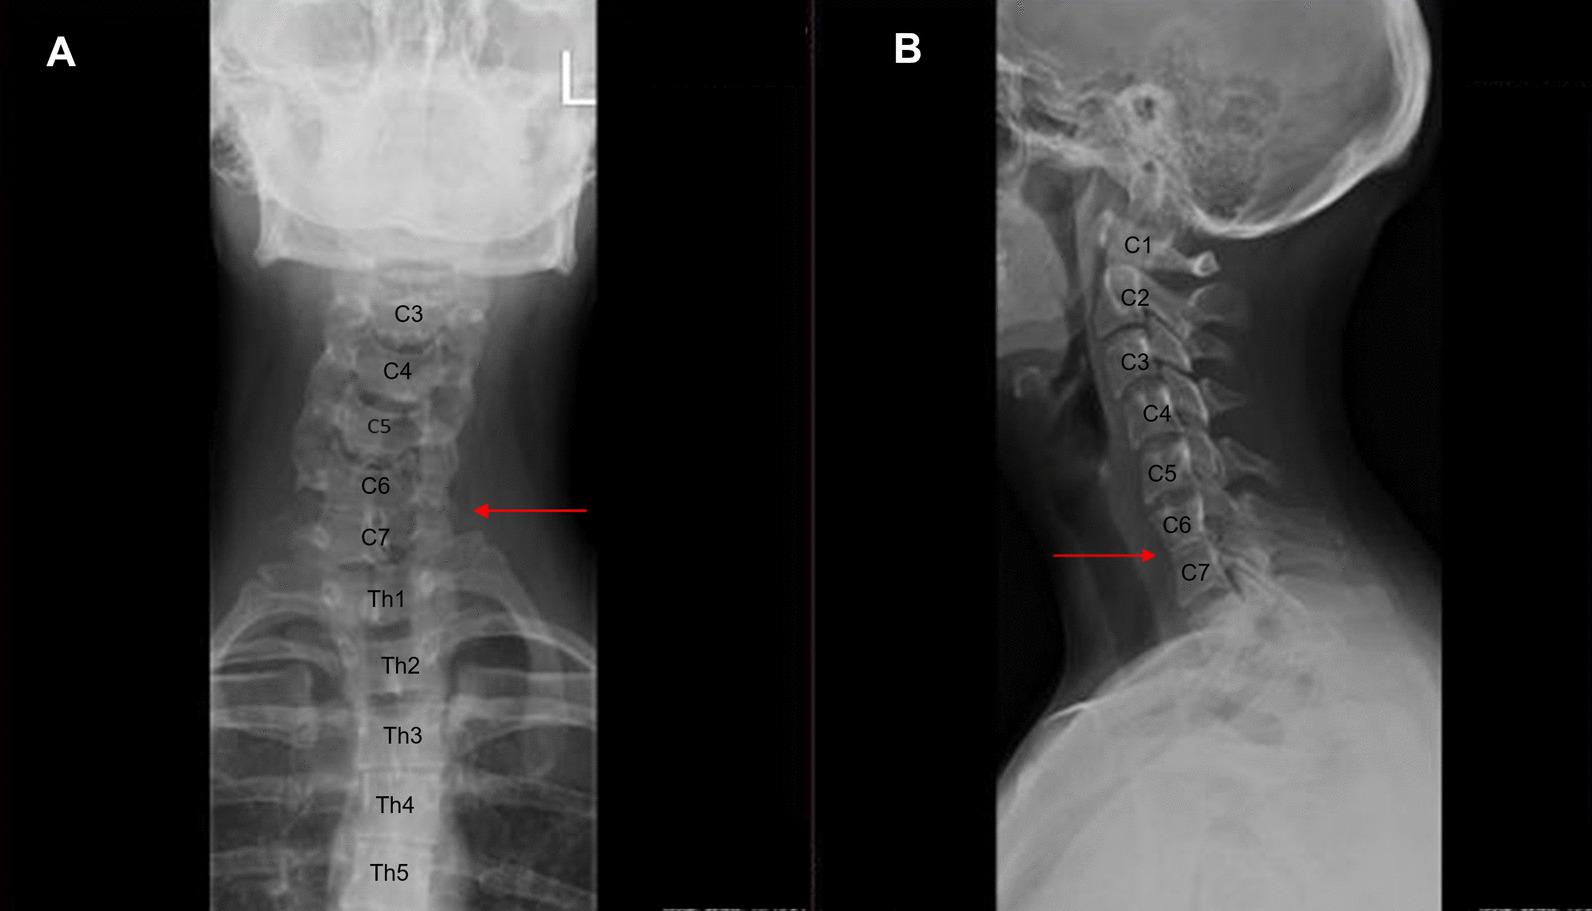

Vertebral malformations (VMs) pose a significant global health problem, causing chronic pain and disability. Vertebral defects occur as isolated conditions or within the spectrum of various congenital disorders, such as Klippel-Feil syndrome, congenital scoliosis, spondylocostal dysostosis, sacral agenesis, and neural tube defects. Although both genetic abnormalities and environmental factors can contribute to abnormal vertebral development, our knowledge on molecular mechanisms of numerous VMs is still limited. Furthermore, there is a lack of resource that consolidates the current knowledge in this field. In this pioneering review, we provide a comprehensive analysis of the latest research on the molecular basis of VMs and the association of the VMs-related causative genes with bone developmental signaling pathways. Our study identifies 118 genes linked to VMs, with 98 genes involved in biological pathways crucial for the formation of the vertebral column. Overall, the review summarizes the current knowledge on VM genetics, and provides new insights into potential involvement of biological pathways in VM pathogenesis. We also present an overview of available data regarding the role of epigenetic and environmental factors in VMs. We identify areas where knowledge is lacking, such as precise molecular mechanisms in which specific genes contribute to the development of VMs. Finally, we propose future research avenues that could address knowledge gaps.

脊柱畸形(VMs)是一个全球性的健康问题,会导致慢性疼痛和残疾。脊柱缺陷可以是孤立的情况,也可以是各种先天性疾病的谱系中的一部分,如 Klippel-Feil 综合征、先天性脊柱侧凸、脊柱肋骨骺发育不良、骶骨发育不全和神经管缺陷。尽管遗传异常和环境因素都可能导致异常的脊柱发育,但我们对许多 VMs 的分子机制的了解仍然有限。此外,缺乏整合该领域现有知识的资源。在这篇开创性的综述中,我们对 VMs 的分子基础以及与 VMs 相关的致病基因与骨发育信号通路的关联的最新研究进行了全面分析。我们的研究确定了 118 个与 VMs 相关的基因,其中 98 个基因参与了形成脊柱的关键生物途径。总的来说,该综述总结了 VMs 遗传学的现有知识,并为生物途径在 VMs 发病机制中的潜在作用提供了新的见解。我们还概述了关于表观遗传和环境因素在 VMs 中的作用的现有数据。我们确定了知识匮乏的领域,例如特定基因在 VMs 发育中的作用的精确分子机制。最后,我们提出了可能解决知识空白的未来研究方向。